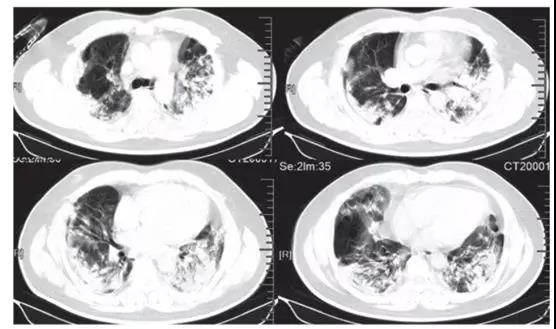

ICU患者入院时胸部CT图像的典型发现,是双侧多发小叶和亚段实变(见下图)。